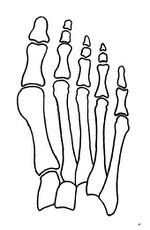

Primus varus deformity is the leaning of the first metatarsal bone away from the second metatarsal and towards the opposite foot (Fig. 1). As it leans over, its head sticks out to form the bunion bump and it also widens the forefoot to cause shoes feeling too tight. Thus when bunion pain becomes unmanageable, surgical correction is to narrow the forefoot by repositioning of the first metatarsal head back to its normal position. This can be done by osteotomy (bone-breaking), soft tissue (non-osteotomy) or fusion techniques.[citation needed]